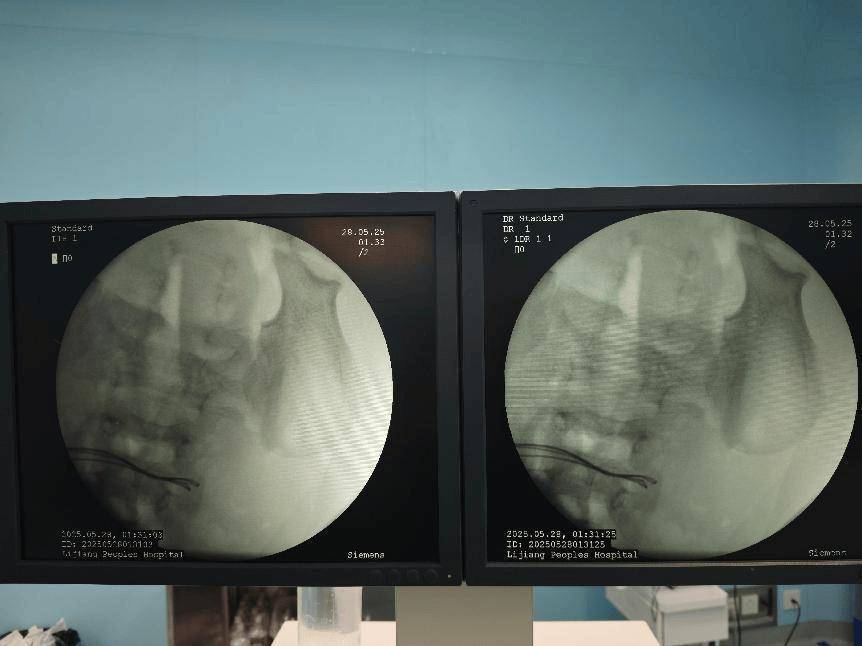

术前腹部DR片

经过初步的影像学检查,医疗团队发现:病人体内竟然有37颗异物,连在一起呈手串状,并伴有小肠穿孔。